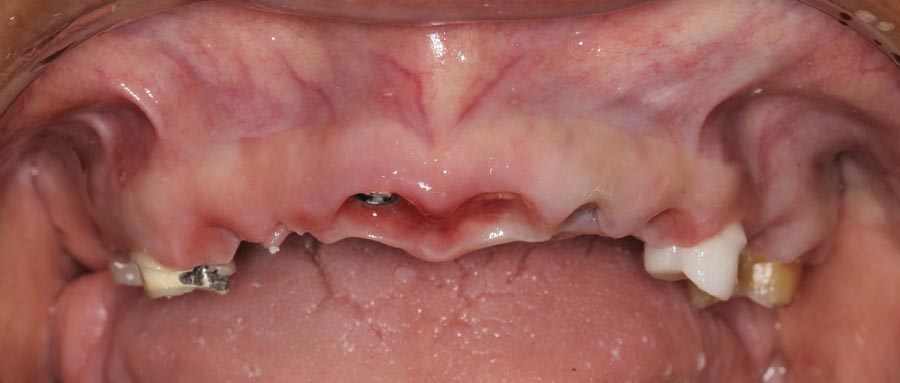

Smile GalleryImplant RestorationsFull Mouth Implant Restoration Full arch zirconia implant bridge (full smile) 1 of 37 Pre-op full smile Pre-op lips retracted Pre-op panoramic x-ray Extraction of strategic teeth Placement of implants Extraction of some remaining teeth after verification of adequate implant stability Occlusal view Post-op panoramic x-ray Immediately fabricated provisional restoration (tissue side view) Immediately fabricated provisional restoration (occlusal side view) Immediate provisional delivered on day of surgery Immediate provisional 2 weeks later Scalloped tissue developed from the provisional at 2 weeks Jig used for making a master impression Provisional in place (full smile) Provisional in place (lips retracted) Provisional in place (right side) Provisional in place (left side) Wax try-in (full smile) Wax try-in (right side full smile) Wax try-in (left side full smile) Wax try-in (full face, lips together) Wax try-in (full smile) Wax try-in (right side) Wax try-in (left side) Wax try-in (lips retracted) Full arch zirconia implant bridge on master cast (frontal view) Full arch zirconia implant bridge on master cast (occlusal view) Implant positions and soft tissue representation on master cast (occlusal view) Soft tissue representation on master cast (frontal view) Full arch zirconia implant bridge (tissue side view) Soft tissues on day of delivery (occlusal view) Soft tissues on day of delivery (frontal view) Full arch zirconia implant bridge delivered (lips retracted) Full arch zirconia implant bridge (lips retracted, close up) Post treatment panoramic x-ray Full arch zirconia implant bridge (full smile)